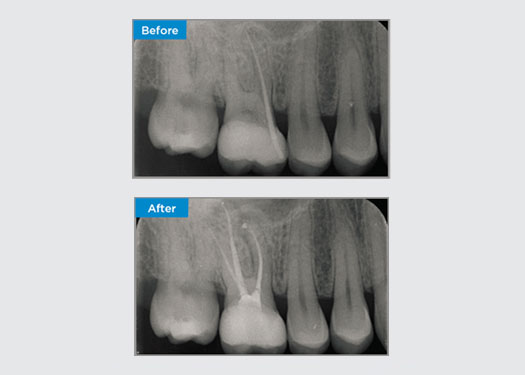

Una paciente de 35 años se presentó después de la derivación de un especialista en periodoncia. Durante la evaluación de endodoncia inicial, la paciente mencionó que se había realizado el alargamiento de la corona, antes de la colocación de la corona en la pieza dental 16, dos años antes. Dos meses antes de que se presentara a la consulta, la paciente había notado una hinchazón de la encía palatina. El odontólogo general de la paciente había descubierto una bolsa periodontal de 7 mm adyacente al tracto sinusal palatino asociado con la pieza dental 16. La paciente fue derivada a un especialista en periodoncia. El periodoncista le diagnosticó una lesión endodóntica principal - periodontal secundaria. La paciente presentaba una buena higiene bucal y asistía regularmente a consulta. La pieza dental 16 estaba sensible a la percusión. Se observó que los márgenes de la corona eran satisfactorios y que las bolsas periodontales alrededor de la pieza dental 16 tenían menos de 2 mm de profundidad en la cara bucal; sin embargo, en la superficie palatina, adyacente al tracto sinusal, había una bolsa periodontal aislada de 6,5 mm. Las pruebas térmicas de la pieza dental 16 revelaron una respuesta negativa. La pieza dental 16 tenía factores de riesgo de periodontitis apical, como respuesta negativa a las pruebas térmicas, sensibilidad a la percusión, antecedentes de restauración profunda después de una cirugía de alargamiento de corona y enfermedad periapical identificable por radiografía. La pieza dental 16 no tenía historial de dolor al morder o masticar, lo que puede indicar una grieta que se comunica con la pulpa o los tejidos periodontales. La paciente no tenía factores de riesgo de enfermedad periodontal y no había bolsas anormalmente profundas presentes alrededor de ningún otro diente.

Dr. Omar Ikram, endodoncista, Crows Nest, NSW Australia